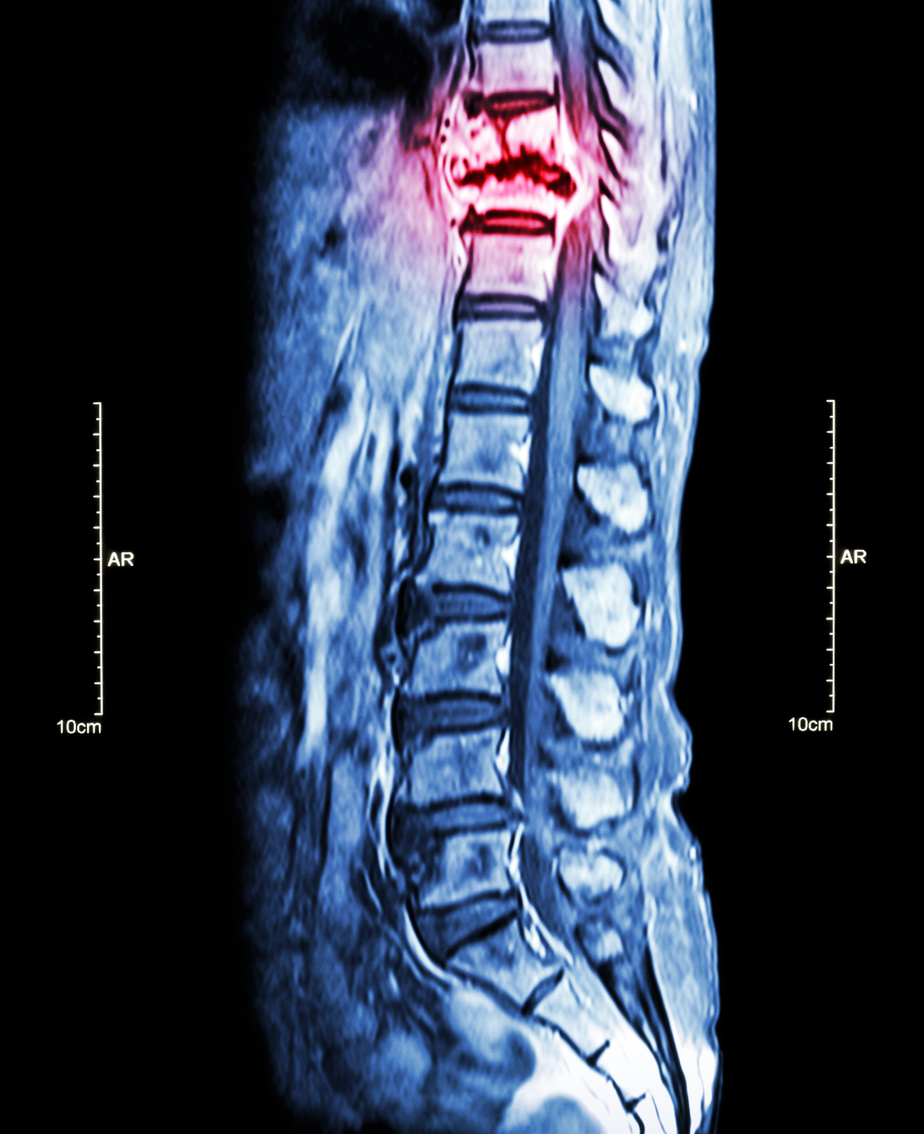

A prognostic scoring system for predicting 1-year survival in patients with advanced cancer and spinal metastases was enhanced with machine learning for greater accuracy, according to the results of a Japanese multicenter study published in Spine.